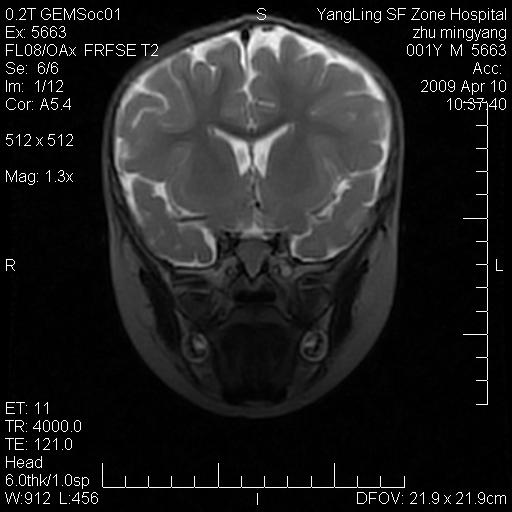

患者:1岁半,两天前外伤收住我院,ct检查小脑占位

考虑星形细胞瘤,建议增强

髓母细胞瘤或血管母细胞瘤,增强后可以鉴别;影像资料见 <。鱼博浪老师的《中枢神经系统ct与mr鉴别诊断》 小脑部肿瘤章节。

髓母细胞瘤或血管母细胞瘤!支持!

支持考虑髓母细胞瘤

考虑----髓母细胞瘤可能性大

考虑髓母细胞瘤或室管膜瘤。

支持髓母细胞瘤。

考虑髓母细胞瘤。

考虑髓母细胞瘤或星形细胞瘤

考虑髓母细胞瘤.

考虑髓母细胞瘤可能性大。

小脑肿瘤.考虑髓母细胞瘤可能.

就病灶部位及临床资料首先考虑髓母.